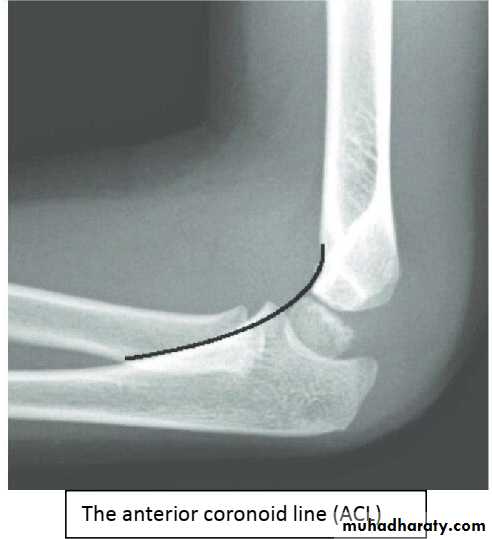

Coronoid line : A line drawn along the anterior border of the coronoid process of the ulna should touch the anterior part of the lateral condyle of the humerus. If lateral condyle appearsposterior to this line, it indicates the posterior displacement of lateral condyle.